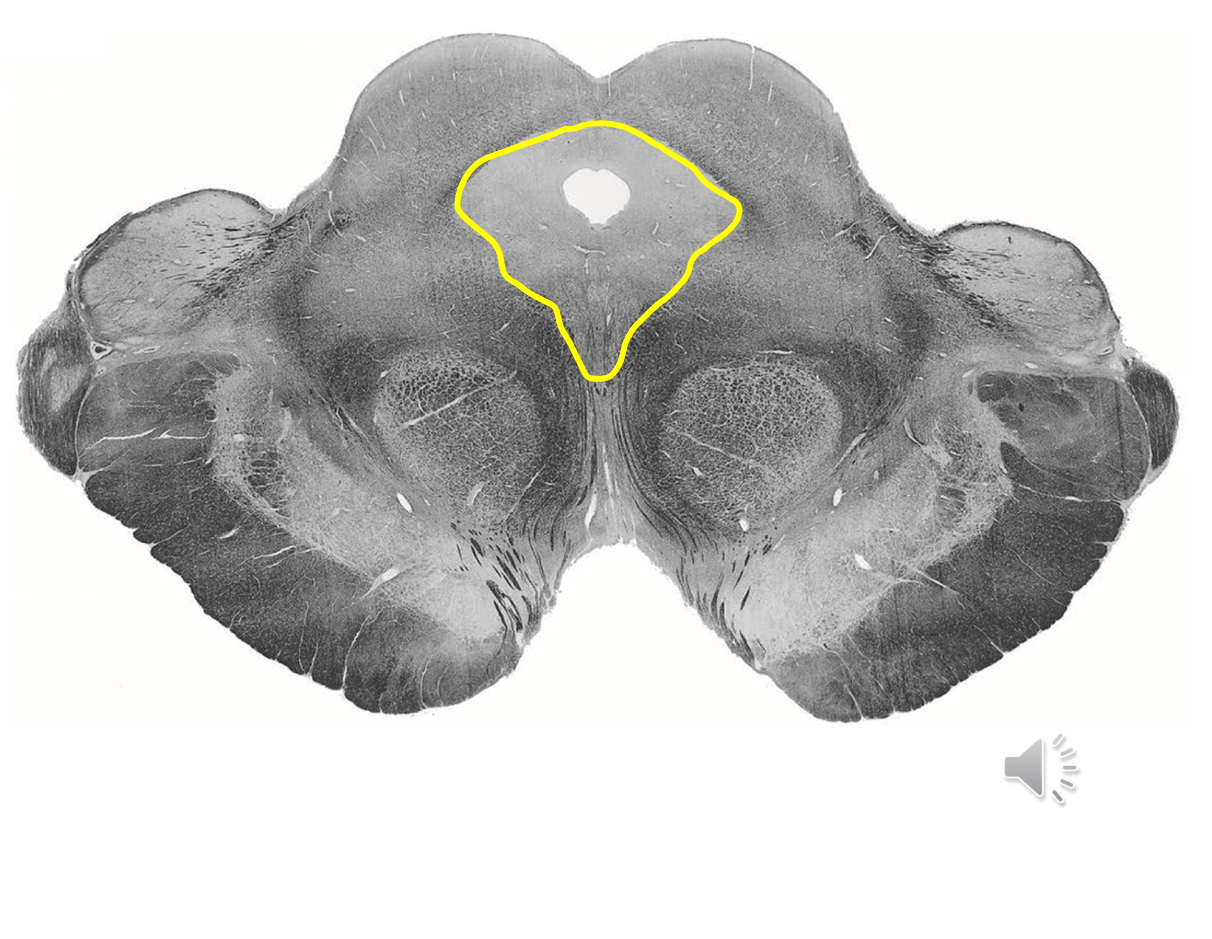

Geisha Caudal midbrain level of inferior colliculus

Boomerang still

Blue medial lemniscus

Red ALS spinothalamic tract

Rostral midbrain level of superior colliculus

Red ALS spinothalamic

Blue Medial lemniscus (DCML)